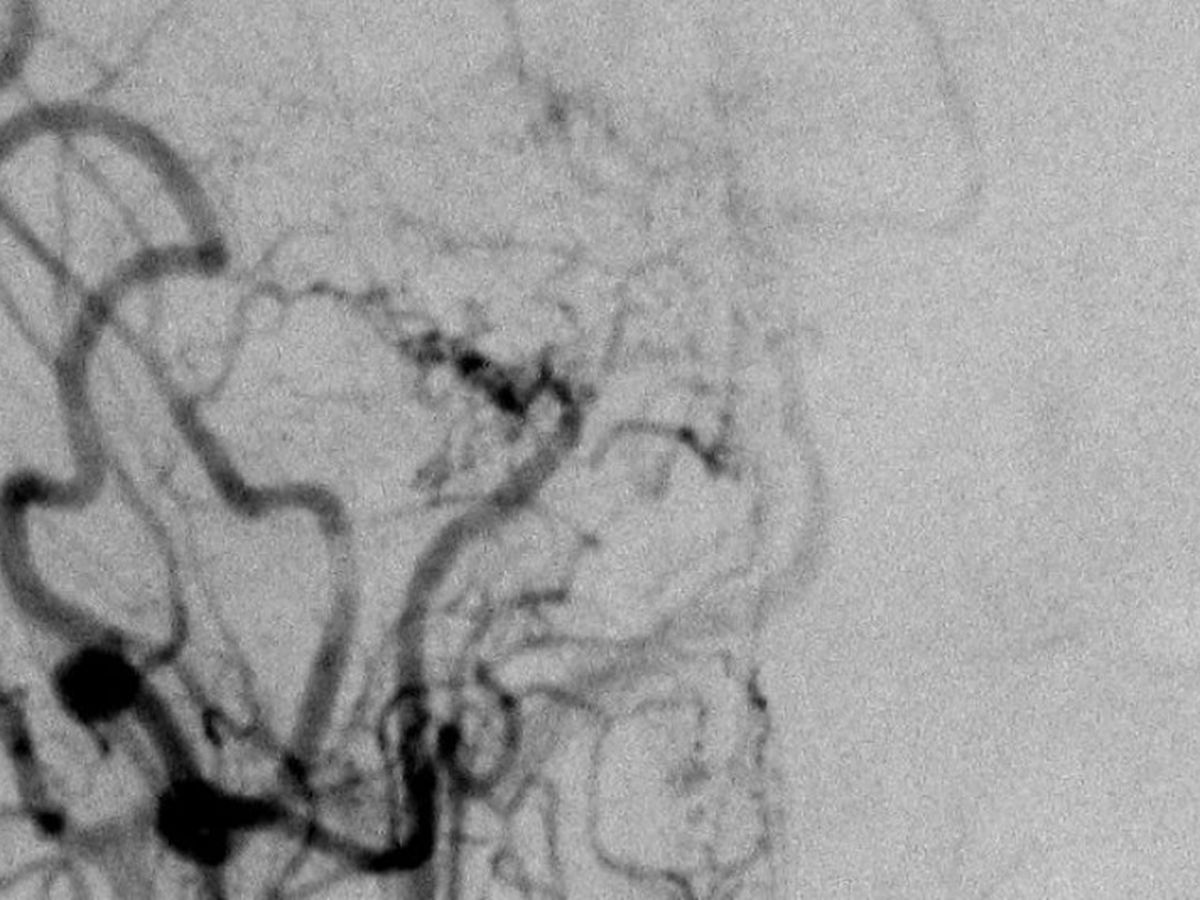

Turns out, I was diagnosed with a rare, progressive and incurable disease called, "moyamoya." The disease causes the arteries connecting to my brain to shrivel and close up in muscle tissue, which causes strokes over time, and gets worse and worse the longer it is left untreated.